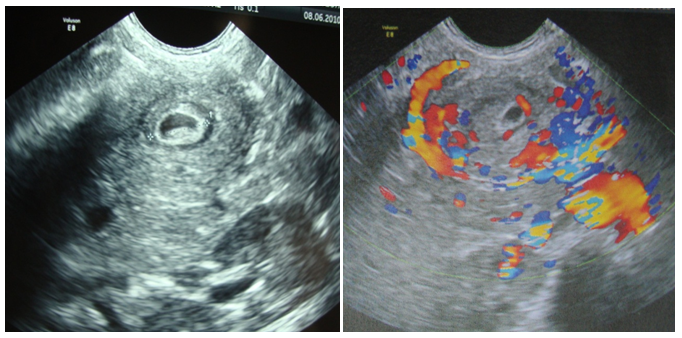

A two year old girl was presented in emergency for paroxystic abdominal pain without vomiting or other signs. The physical exam showed an epigastrium mass of 3cm which is round, tense, smooth and non tender beneath the umbilicus. Biologic exams were normal. Abdominal ultrasound with computer tomography revealed a cystic epigastric mass of 4.3cm with a wall that took contrast (Figure 3). Around this mass there was an ultrasound aspect of volvulus (Figure 4). A barium-meal examination demonstrated delayed gastric emptying through a narrowed pyloric antrum, which was distorted by a non communicating mass (Figure 5). At laparotomy, a cystic mass measuring approximately 4 × 3cm was identified anterior and lateral to the pyloric channel, sharing a common wall. The mass compressed the pyloric channel, resulting in partial gastric outlet obstruction. The duplication cyst did not communicate with the pyloric channel. Most of the cyst was excised, and the mucosa of the remnant cyst wall was cauterized. Histologic examination revealed gastric mucosa with a smooth muscle coat, which was consistent with a pyloric duplication cyst. No aberrant tissue was seen. The postoperative course was uneventful. The patient was asymptomatic 4years later.

Figure 4 Ultrasound aspect of volvulus around the mass.